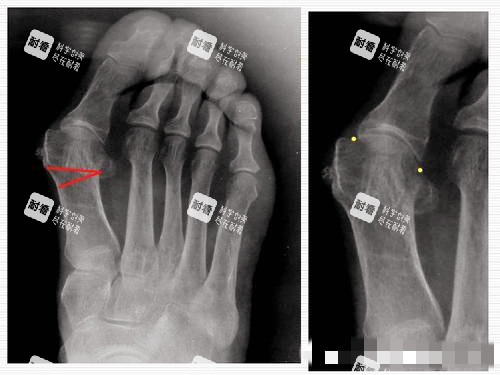

马桂文这边,资历更吓人——1995年就开始研究足病,到现在整整27年!他是北京煤医西坝河医疗美容医院的“头牌”,还是马文足医生集团的建立人,手握31项国内专有,其中21项是自己研发的,10项是和北医三院联合搞的。他开展的“5D微孔弧祛大脚骨技术”,用光导仪器实时监测截骨角度,误差小于0.5度,连重度畸形(外翻角>40°)都能精细矫正。

马桂文:光导复位,精细到“毫米级”

马桂文的“5D微孔弧技术”,主打“可视化”——用光导仪器把脚部内部结构投射到屏幕上,医生边看边操作,截骨角度误差小于0.5度,连骨头上的小凸起都能磨平。术后不用打钢钉,用张力带、骨PDS和盖式生物三重固定,稳固又灵活。